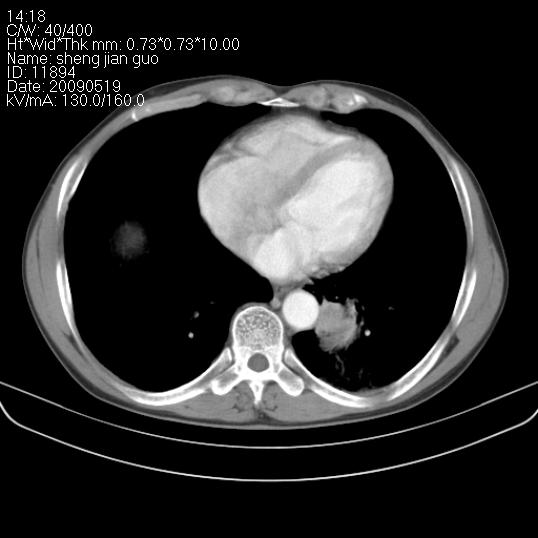

以下是引用zjzjr在2009-5-19 17:25:00的发言:[br]支持楼主考虑,另左肺下叶阻塞性炎症。

以下是引用zhao_bin2008在2009-5-19 17:48:00的发言:[br]支持左肺下叶周围型肺癌并阻塞性肺炎。

以下是引用zsl6918在2009-5-20 7:10:00的发言:[br]左侧中心型肺癌!